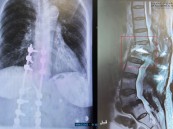

بعد 5 محاولات جراحية لم تنجح.. مستشفى الحبيب بالخبر يُمكّن سبعينية من المشي مجددًا

شهد مستشفى الدكتور سليمان الحبيب بالخبر، إجراء عملية معقدة ومتقدمة لمراجعة "سبعينية" تعرضت لكسر حاد وانفصال في العمود الفقري، جراء إصابتها بانزلاق غضروفي قبل سنوات، وتعقدت حالتها بعد محاولتها للعلاج وخضوعها لــ "5" عمليات في مستشفيات أخرى داخل وخارج المملكة، ...